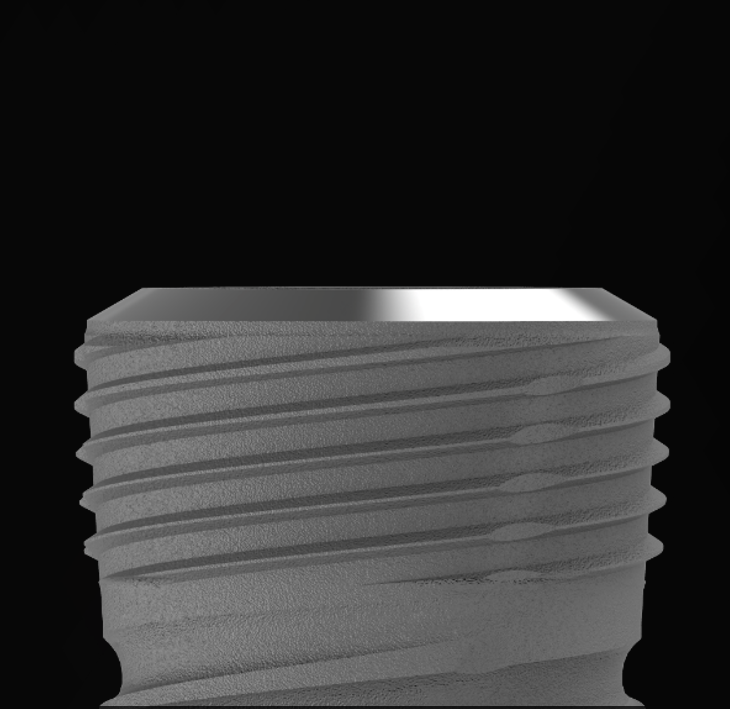

Optimized Thread Geometry for Strong Primary Stability

The dual-thread and coronal microthread design of Implantium II ensures even load distribution across both cortical and cancellous bone. This geometry provides smooth insertion torque and secure primary stability, even in immediate loading or single-tooth cases.

Clinicians can also expect predictable stability in low-density bone due to its controlled insertion characteristics.

Biological Thread for Enhanced Bone Integration

The biological thread design maximizes bone-to-implant contact by promoting natural bone engagement along the thread surface.

Its optimized thread profile allows smooth penetration into bone with minimal stress, encouraging early bone remodeling and strong osseointegration.